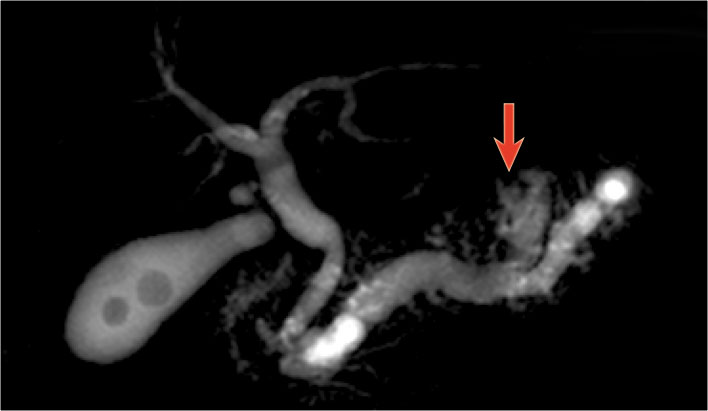

The MRCP shows both a main-duct aswell as a branch-duct IPMN (arrow).